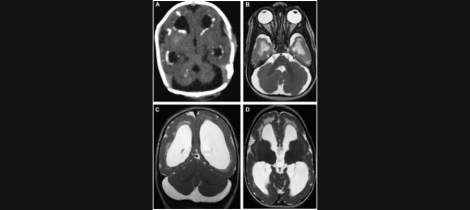

Figure: Neuroimaging of an extreme premature infant. The ventricles are dilated (ventriculomegaly) and there is diffuse cortical and cerebellar atrophy.

The brain exists within the confined space of the skull. Whenever brain tissue is damage and reabsorbed the cavities at the center of the brain (called ventricles) tend to dilate in order to compensate for the tissue deficit. It is almost as if the brain abhors a vacuum and decides to fill reabsorbed tissue by forming a cavity and/or expanding the ventricles. In this regard ventricular expansion remains as a tombstone of earlier brain damage.

Low birth weight infants that die shortly post-term show evidence of hemorrhages, re-absorption of the white matter surrounding the ventricles, and ventricular enlargement. Those that survive and are examined later on in life may show evidence of a malformed cerebral cortex (e.g., many small gyrifications, convolutions that take the form of mushrooms).